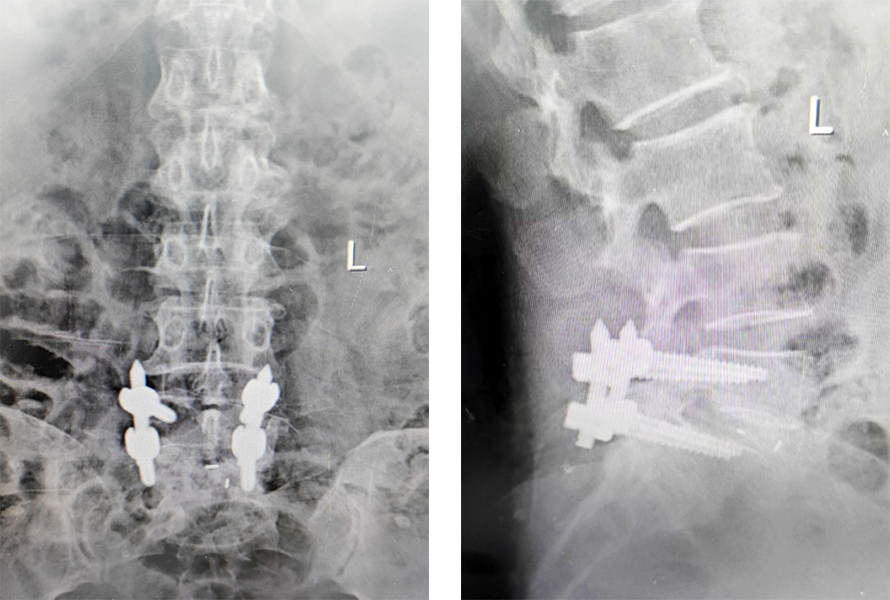

腰椎影像片

經(jīng)朱慧爭主任詳細(xì)查體

閱過之前拍的片子后

發(fā)現(xiàn)姥姥腰5椎體滑脫

便形容說

就像一摞書

上面的向前滑脫

但還沒掉下來

需及時復(fù)位并固定

術(shù)后影像